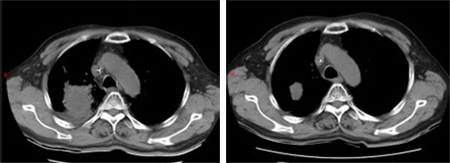

2024年7月,老李的右上肺原发灶增大,支气管再次狭窄。我们立刻给患者复查了气管镜。镜下没有新生物,只有黏膜充血水肿;穿刺也只看到变性坏死组织。影像进展、病理阴性,到底是耐药还是感染?我们启动了全院多学科讨论,最后决定:按耐药处理,执行“化疗+免疫”的二线方案。2个周期后,病灶再次显著缩小,疗效评估达到部分缓解。6周期后病灶继续缩小。老李的咳嗽、憋气症状完全消失,吃得好、睡得香,笑称:“我又回到了没得病的状态。”

化疗+免疫治疗前;化疗+免疫治疗2周期后